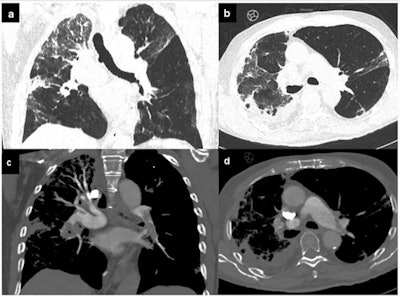

Pulmonary embolism. COVID-19 patient with dyspnea, increased D-dimer levels, and oxygen saturation < 93. Chest CT evidenced ground-glass opacity with interstitial thickening of the interlobular and intralobular septa, together with pleural effusion (a, b). After contrast media injection, pulmonary embolism was found in the left upper lobar branch, the left inferior lobar branch, and the segmental arteries for the left inferior pulmonary lobe and pulmonary embolism of the interlobar arteries for the inferior right lobe, probably extended to the subsegmentary arteries (c, d)."We're also proceeding with our longitudinal studies in patients with active disease," corresponding author Prof. Marco Francone, PhD, told AuntMinnieEurope.com.